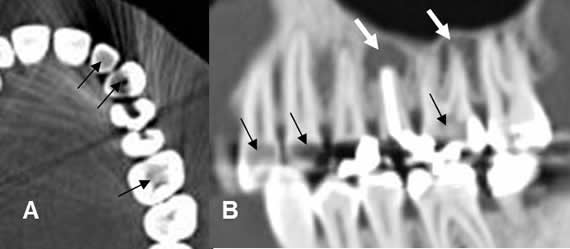

Fig 35. Caries múltiples.

A: TAC axial y B: TAC reconstrucción sagital. Varias zonas hipodensas que reemplazan el cemento y la pulpa de los dientes (Flechas negras) y corresponden a caries. Existe perilucencia apical asociada, por enfermedad endodental (Flechas gruesas blancas).